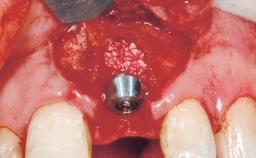

A 42-year-old female patient was referred to our clinic at the School of Dentistry of the University of São Paulo in November 2004, presenting a deficient restoration in the upper left central incisor. The clinical examination revealed no gingival retraction or any signs of gingival inflammation and, therefore, previous periodontal treatment was not considered. The patient presented a high lip line at full smile and a thin tissue biotype. This combination characterized a high-risk situation from an anatomic point of view, which required careful preoperative planning and cautious surgical execution.

Placement Protocol Immediate implant placement

Tooth Site Maxillary incisor or canine

Socket Morphology Single-root socket

Socket Integrity Sufficient, with intact bone walls

Bone Volume Sufficient, with intact walls

Loading Protocol Immediate